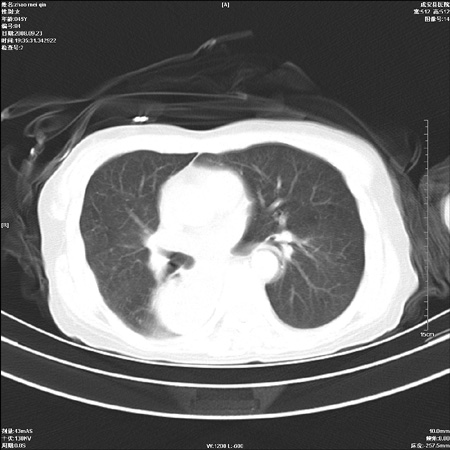

标题: CT15861:女 60 外伤后1小时 胸疼 [打印本页]

标题: CT15861:女 60 外伤后1小时 胸疼

外伤后1小时 胸疼 是外伤后引起的吗?

食道扩张明显下端逐渐变窄,倒像贲门失迟缓

食道ca术后胸腔胃,右肺挫伤?

食道扩张明显下端逐渐变窄,大量食物存留,象贲门失迟缓症。